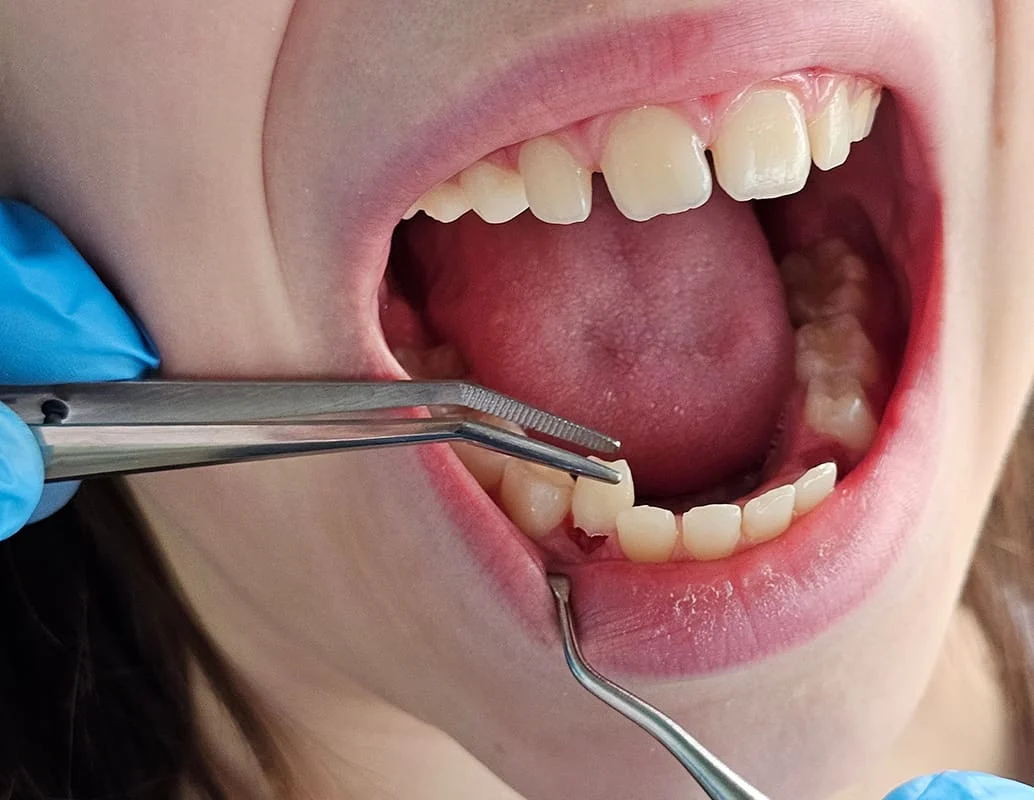

یکی از سوالات رایج در بین بیماران، اطلاع از هزینه خدمات دندانپزشکی است. در مورد کشیدن دندان در جوانرود، قیمت نهایی به عواملی مانند نوع دندان، روش کشیدن (ساده یا جراحی)، وجود عفونت یا نهفتگی دندان بستگی دارد.

| کشیدن ساده | برای دندانهای قابل مشاهده، بدون جراحی |

| کشیدن با جراحی | برای دندانهای نهفته یا شکسته در زیر لثه |

| کشیدن دندان عقل | ممکن است ساده یا همراه با جراحی باشد |